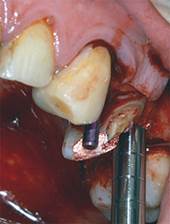

In zwei bestehende Einzelzahnlücken werden je 1 Implantat gesetzt, unter anderem mit Hilfe der Osteotomtechnik zur Verbesserung des Knochenangebotes. -